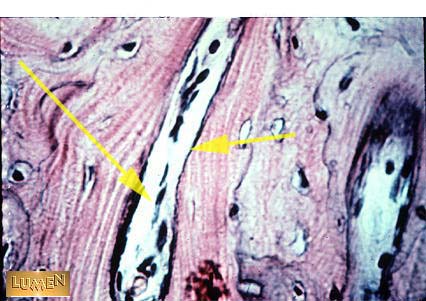

What is this structure?

Blood Vessel